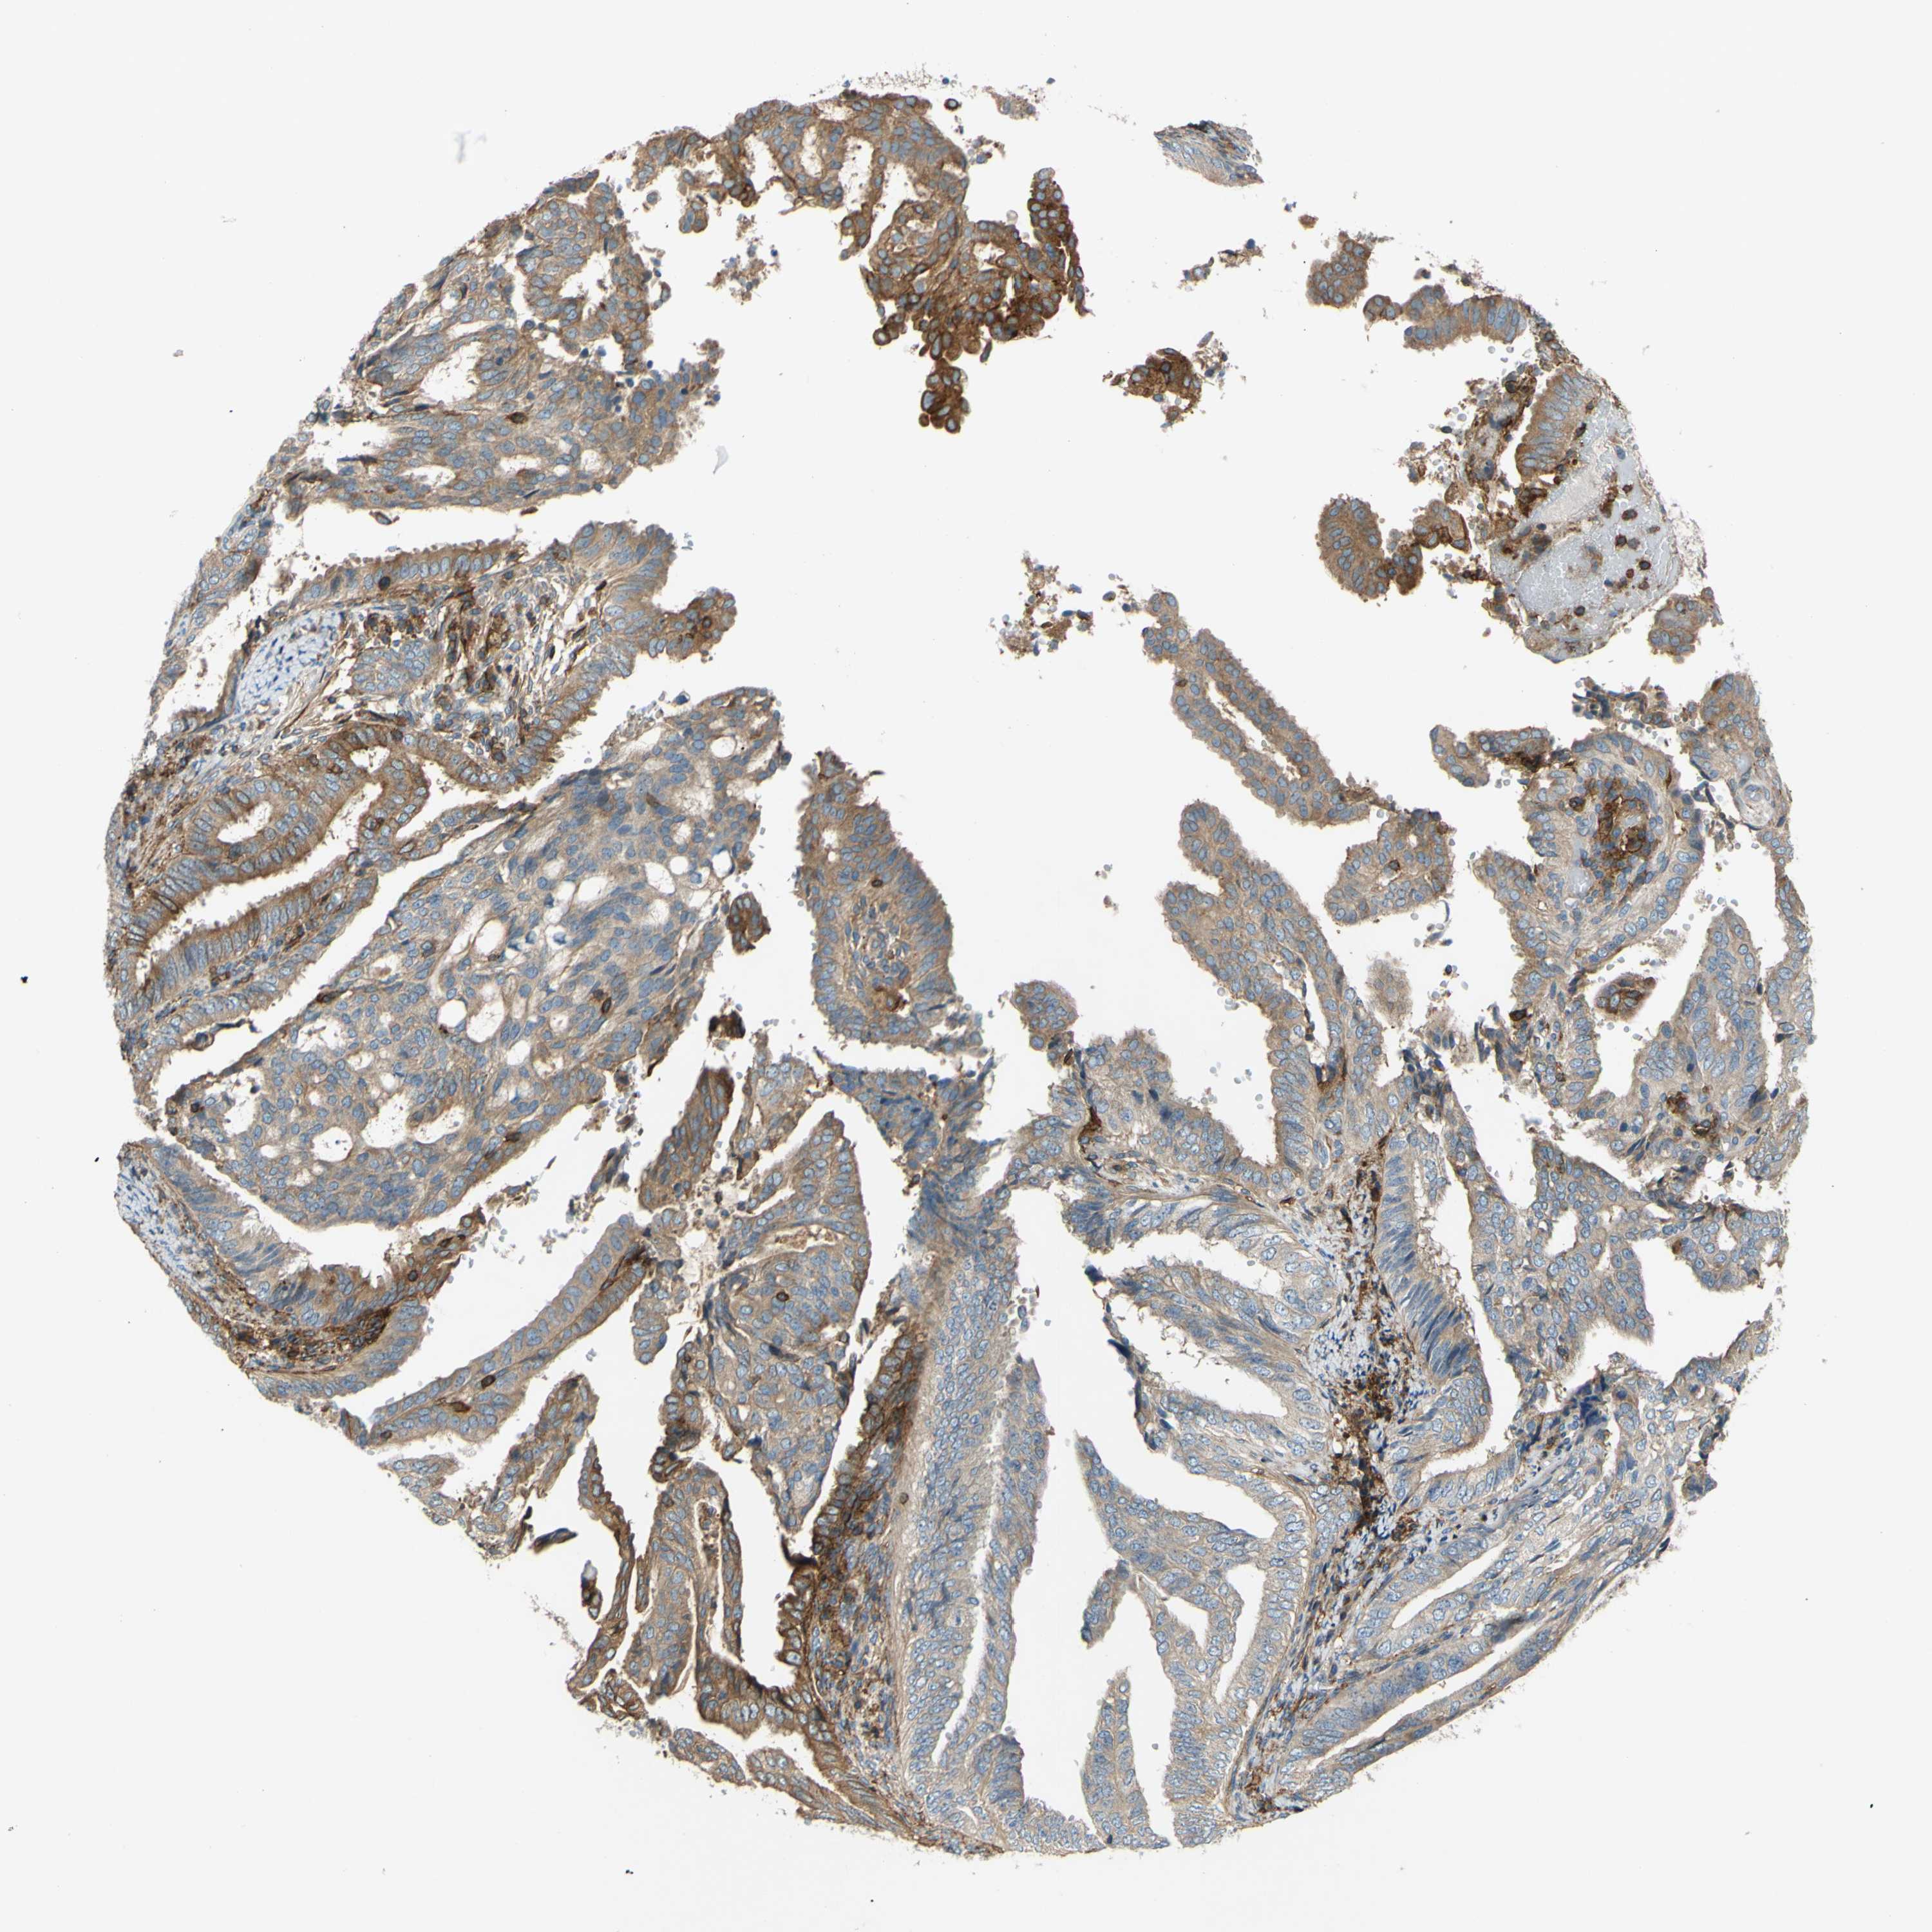

ENDOMETRIAL CANCER - Protein expressioni

A mouse-over function shows sample information and annotation data. Click on an image to view it in a full screen mode. Samples can be filtered based on level of antibody staining by selecting one or several of the following categories: high, medium, low and not detected. The assay and annotation is described here.

Note that samples used for immunohistochemistry by the Human Protein Atlas do not correspond to samples in the TCGA dataset.

Antibody stainingi

Antibody staining in the annotated cell types in the current human tissue is reported as not detected, low, medium, or high, based on conventional immunohistochemistry profiling in selected tissues. This score is based on the combination of the staining intensity and fraction of stained cells.

Each image is clickable and will lead to virtual microscopy that enables deeper exploration of all samples and also displays staining intensity scores, fraction scores and subcellular localization as well as patient and tissue information for each sample.

Antibody HPA010136

Antibody CAB004372

Staining

High

Medium

Low

Not detected

Intensity

Strong

Moderate

Weak

Negative

Quantity

>75%

75%-25%

<25%

None

Location

Nuclear

Cytoplasmic/membranous

Cytoplasmic/membranous,nuclear

Adenocarcinoma, NOS

Neoplasm, malignant, NOS